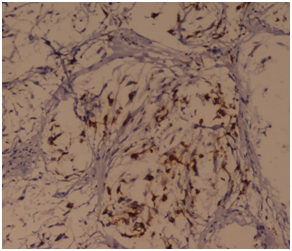

A 50years old female presented to the surgical outpatients department with complaints of painless lump in the left breast for the last 5months. On inspection a swelling was seen in the upper outer quadrant. Skin overlying the swelling appeared to be normal and the nipple was slightly deviated medially. On palpation a hard, painless mass of size 4x3cms was palpated in the breast with irregular margin, fixed to the underlying tissue and attached to overlying skin. Overlying skin showed peau de orange. Left axilla showed no enlarged lymph nodes. On mammography of the left breast, the swelling showed areas of microcalcification. Routine blood investigation showed increased leucocyte count. X-ray of pelvis and spine show no evidence of distant metastasis. On fine needle aspiration cytology, sheets and nests of pleomorphic atypical ductal cells was seen, with nuclear hyperchromasia, increased nuclear cytoplasmic ratio, prominent nucleoli and moderate amount of eosinophilic cytoplasm. A foci of benign spindle cells with wavy nuclear morphology was also seen. Based on the investigations, a diagnosis of infiltrating ductal carcinoma is made and the patient underwent modified radical mastectomy. On histopathology, grossly the tumor was located in the upper outer quadrant measuring 4.5x3x1.5 cm in dimension. A subareolar extension of tumour was seen below the nipple-areola complex measuring 2x1x0.7cm in dimension (Figure 1). Cut section showed a greyish hard solid tumor with areas of haemorrhage and necrosis. Six lymph nodes were also dissected. On microscopy, sheets or whorls of tumor cells was seen with cellular and nuclear pleomorphism, hyperchromatic nucleus and high N/C ratio with prominent nucleoli and moderate amount of eosinophilic cytoplasm (Figure 2). A foci of fascicular pattern of proliferation of peripheral nerves in wavy serpentine configuration and fibroblasts was seen associated with the tumor (Figure 3). Resection margin and nipple areola complex was free from any tumor deposits. Lymph nodes showed only reactive changes. On immunohistochemistry, the foci of nerve proliferation showed diffuse positivity with S100 (Figure 4). A final diagnosis of infiltrating ductal carcinoma with neurofibroma was given. Adjuvant chemotherapy with 6 cycles of Cisplatin (50mg) was administered along with 50G of Co-60 teletherapy. After 12months of follow up, no recurrent disease was noted.

Figure 4 On Immunohistochemistry, the foci of nerve proliferation showed diffuse positivity with S100. IHC S 100 x 40X.